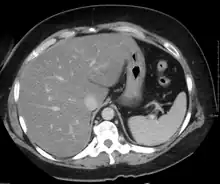

Liver steatosis (fatty liver disease) as seen on CT

Imaging studies are often obtained during the evaluation process. Ultrasonography reveals a "bright" liver with increased echogenicity. Pocket-sized ultrasound devices might be used as point-of-care screening tools to diagnose liver steatosis. [30] [31] Medical imaging can aid in diagnosis of fatty liver; fatty livers have lower density than spleens on computed tomography (CT), and fat appears bright in T1-weighted magnetic resonance images (MRIs). Magnetic resonance elastography, a variant of magnetic resonance imaging, is investigated as a non-invasive method to diagnose fibrosis progression.[32] Histological diagnosis by liver biopsy is the most accurate measure of fibrosis and liver fat progression as of 2018.[8] Conventional imaging methods, such as ultrasound, CT and MRI, are not specific enough to detect fatty liver disease unless fat occupies at least 30% of the liver volume.[33]